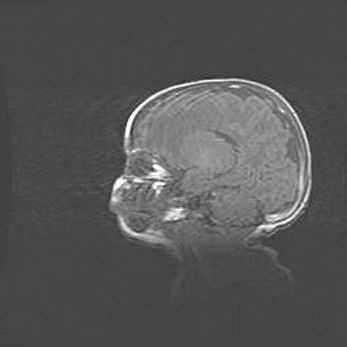

Мальформация Денди-Уокера. Киста задней черепной ямки.

Агенезия мозолистого тела.

Возраст: 2,5 месяца

Вес: 2420 г

Пол: женский

Окружность головы: 37 см

Срок гестации: 32 недели

Мальформация Денди—Уокера — редкий вид патологии ЦНС, представляющий собой врожденный порок развития каудального отдела ствола и червя мозжечка, ведущий к неполному раскрытию срединной (Мажанди) и латеральных (Лушка) апертур IV желудочка мозга. Для этогно синдрома характерна триада симптомов: гипотрофия червя мозжечка и/или полушарий мозжечка, кисты задней черепной ямки, гидроцефалия различной степени. В 70% случаев порок сочетается и с другими аномалиями головного мозга, в частности с агенезией мозолистого тела.